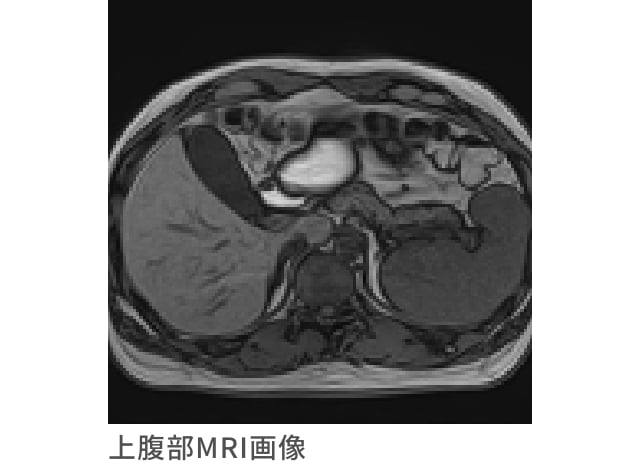

上腹部MRI検査

肝臓、膵臓、胆のうの疾患をより正確に発見するための有効な検査です

超音波検査とは異なった視点で、肝臓・膵臓・胆のうを中心とした上腹部をくまなく検査します。

超音波検査の弱点である、空気(肺の空気や消化管の空気など)や骨の影響を受けることなく、高い精度で小さな病変の発見に有効です。

また、「MRCP(MRlによる胆管膵管の撮影)」検査を併用して行いますので、肝臓から十二指腸に繋がる胆道(胆管・胆のう)や膵臓の中を通る膵管を細かく検査できます。